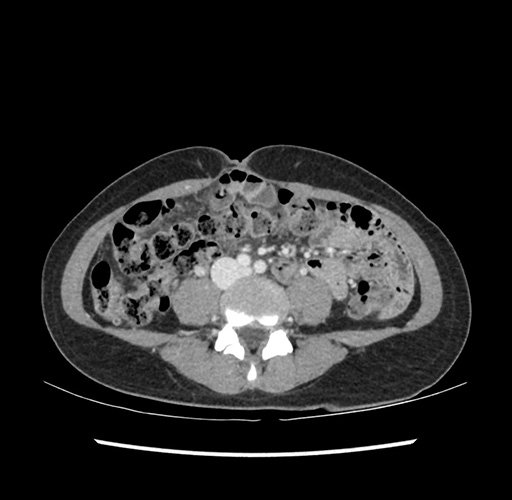

Imaging Analysis

Look through the patient's CT scan to identify any areas of concern for the necessary procedure.

Based on your CT findings, which issue(s) would give reason for "planned slowing down moment(s)" in this case?

Considering a standard left lateral sectionectomy procedure, what step(s) of the operation would you do differently in this case ?